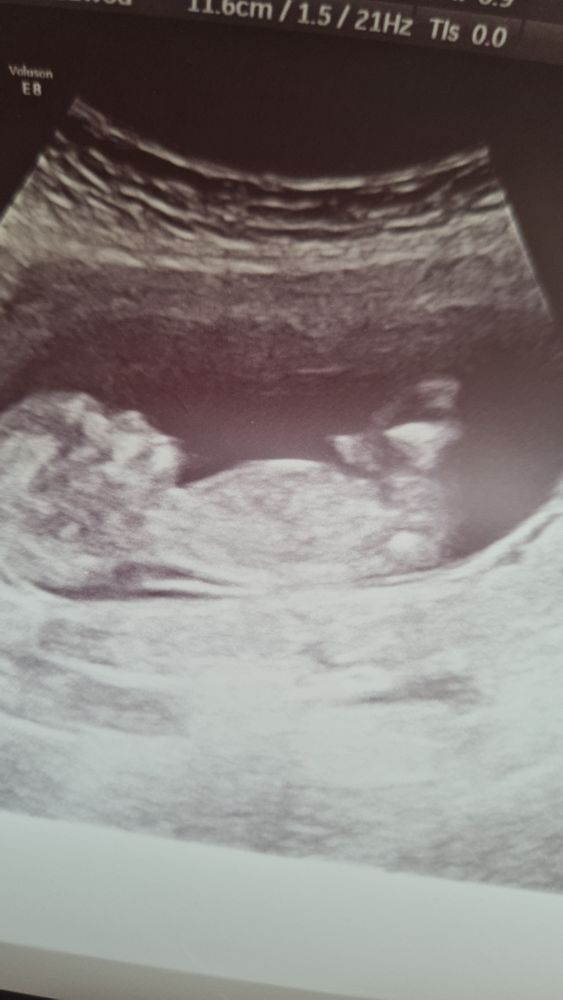

Узи 12 недель

Срок ровно 12 нед,по узи 12.4...КТР 61см, сердцебиение 165

На первом фото непонятно то-ли бугорок то-ли пуповина... Врач сказала непонятно совсем,может больше и к мальчику) так долго ждать ещё до 20 нед)))